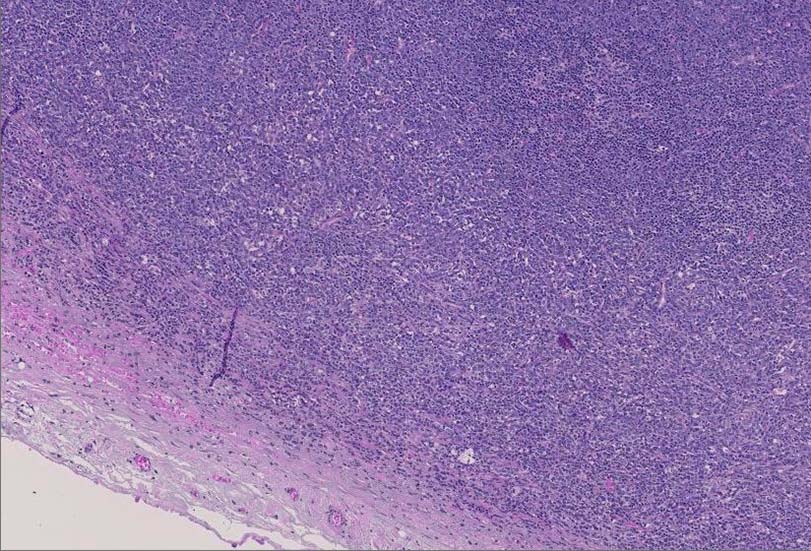

腫大したリンパ節, 20x17mm. 萎縮した胚中心をもつ濾胞が散在する. 一見, Castleman病様の像. よく見ると, 線維化し軽度に肥厚した被膜下に小リンパ球の乏しい, 低倍で明るくみえる領域を視認できる.(サムネイル画像をクリックで大きな画像がみられます)